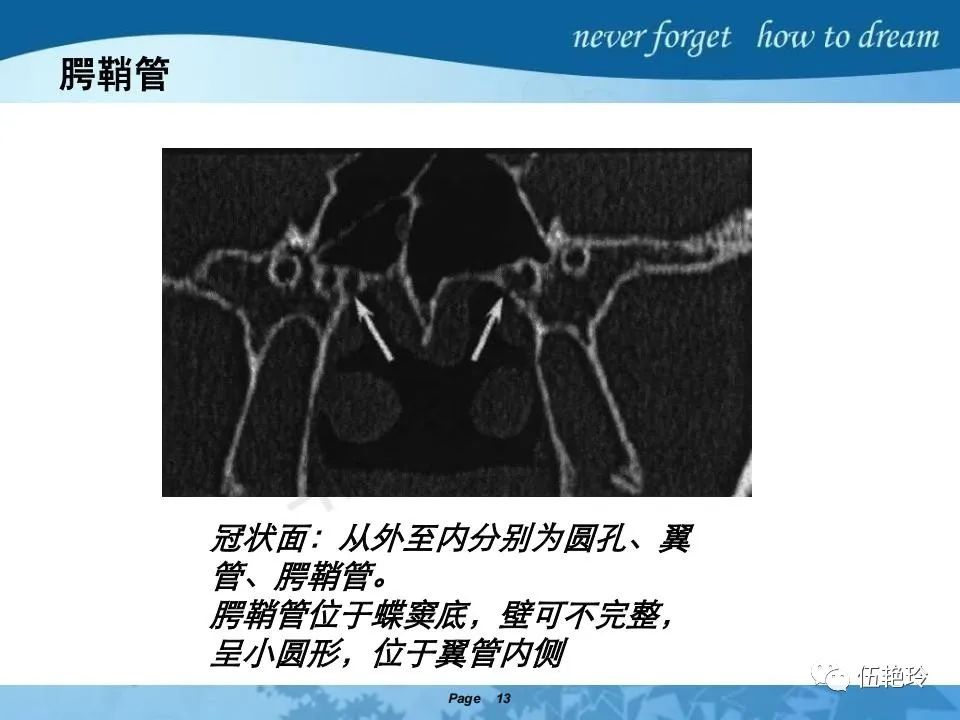

翼腭窝的解剖结构与鼻咽癌侵犯